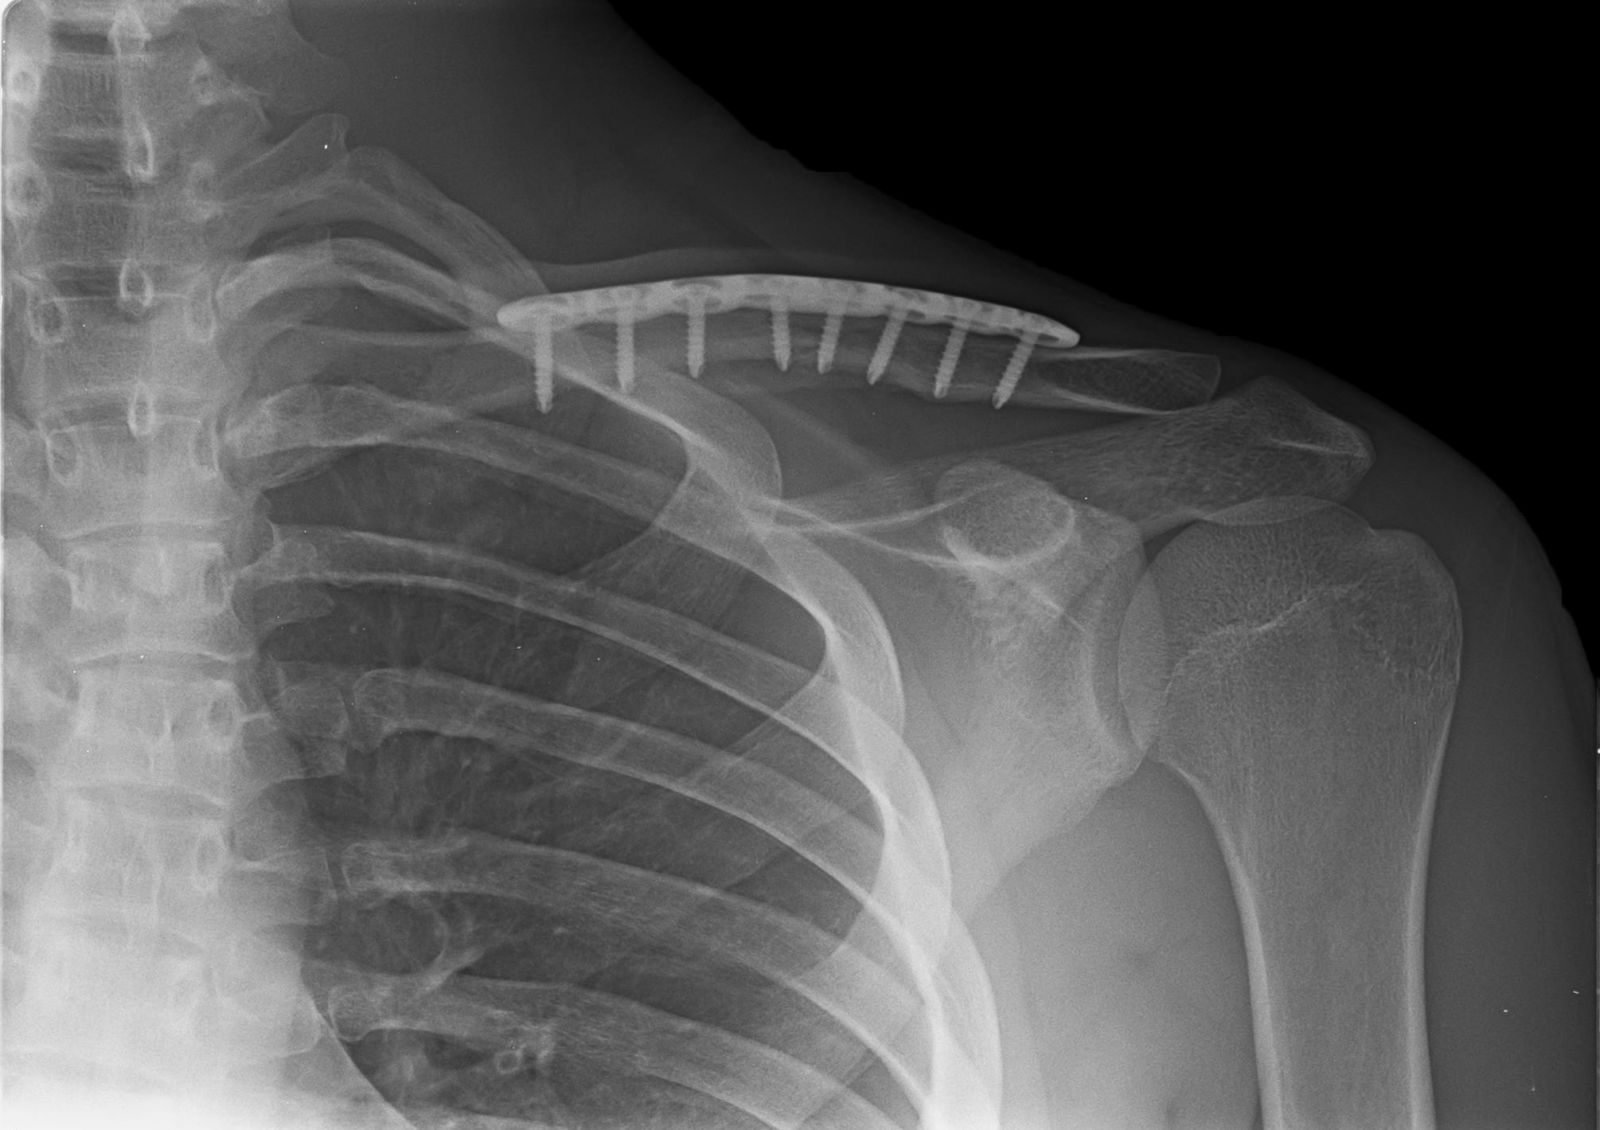

Ανοικτή ανάταξη και εσωτερική οστεοσύνθεση. Αυτή είναι η διαδικασία που χρησιμοποιείται πιο συχνά για τη θεραπεία των κατάγματος της κλείδας. Τα θραύσματα των οστών αρχικά επανατοποθετούνται (ανατάσονται) στην κανονική τους ευθυγράμμιση. Τα κομμάτια του οστού στη συνέχεια συγκρατούνται στη θέση τους με πλάκα και βίδες. Μετά από χειρουργική επέμβαση, μπορεί να παρατηρήσετε μια μικρή περιοχή του δέρματος κάτω από την τομή να είναι μουδιασμένη. Αυτό το μούδιασμα θα γίνει λιγότερο αισθητό με το πέρασμα του χρόνου. Επειδή η κλείδα βρίσκεται ακριβώς κάτω από το δέρμα, μπορεί να αισθανθείτε την πλάκα κάτω από το δέρμα σας. Οι πλάκες και οι βίδες δεν αφαιρούνται συνήθως εκτός εάν προκαλούν δυσφορία.